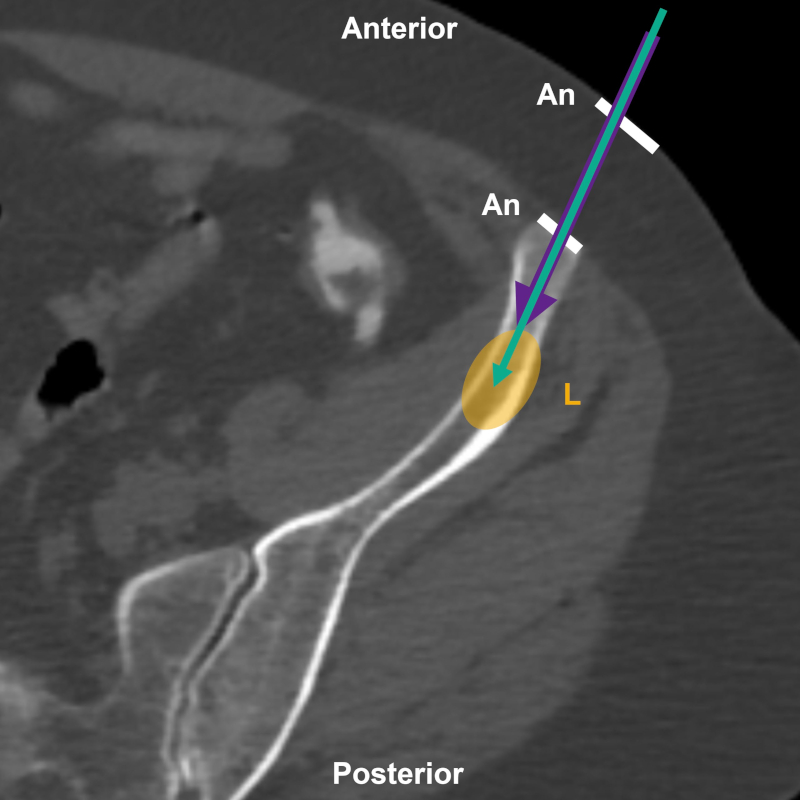

Figura 2

Esquema sobre TC, corte axial de hueso ilíaco izquierdo, para BP coaxial. Aguja introductora (flecha violeta), aguja de biopsia (flecha turquesa), sitios de infiltración anestésica (An) y lesión (L).